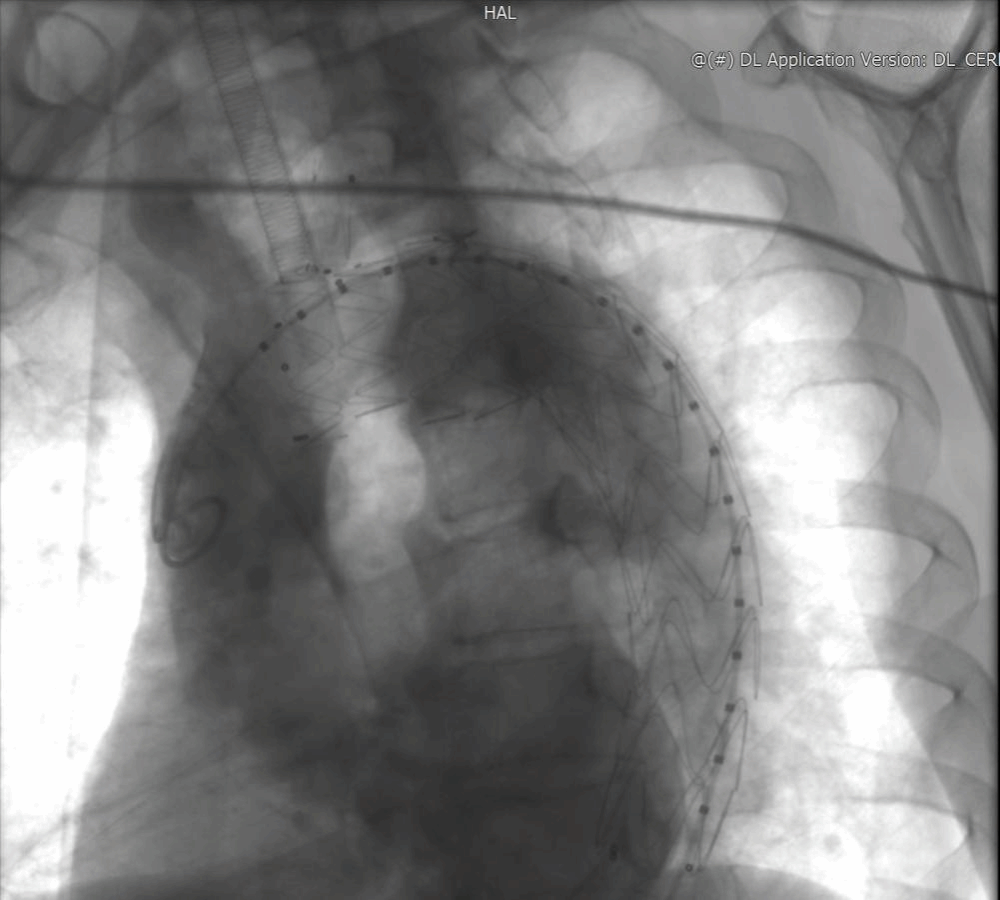

吴大叔回忆,术前多学科会诊(MDT)时,麻醉、心外、血管外、重症医学科专家逐一敲定细节:从术前评估到应急手术预案,甚至细化到导丝通过血管的路径。手术当天,邓捷主任带领刘小军、韩婕、张恒医生团队身着 30 斤铅衣,在 DSA 设备引导下精准操作:先将定制支架接入左颈总动脉,再以支架为 “坐标” 体外开窗,最后植入左锁骨下动脉支架。“最紧张的是造影那一刻,看到血管通了、瘤子被隔绝,大家才松了口气。” 主治医师刘小军说,整场手术耗时 2 小时,全程无大出血、无血管损伤。术后第 2天,吴大叔就能自主活动肢体;术后第三天,各项指标正常,顺利出院。“原以为要躺半个月,现在能买菜做饭,跟没生病一样!” 出院时,他特意给邓捷主任团队鞠了一躬。